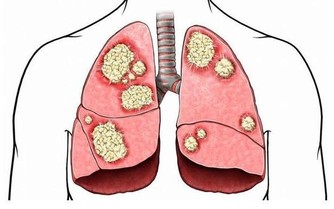

口辣:指口內常覺辛辣或舌體麻辣,常由肺熱或胃熱引起;肺熱者常見伴有鼻咽乾燥、咳吐粘稠黃痰等症狀,宣清肺瀉熱,胃熱者常見伴有口舌乾燥、消谷善飢、胃脘灼熱、大便燥結等症狀,宣清胃瀉火。